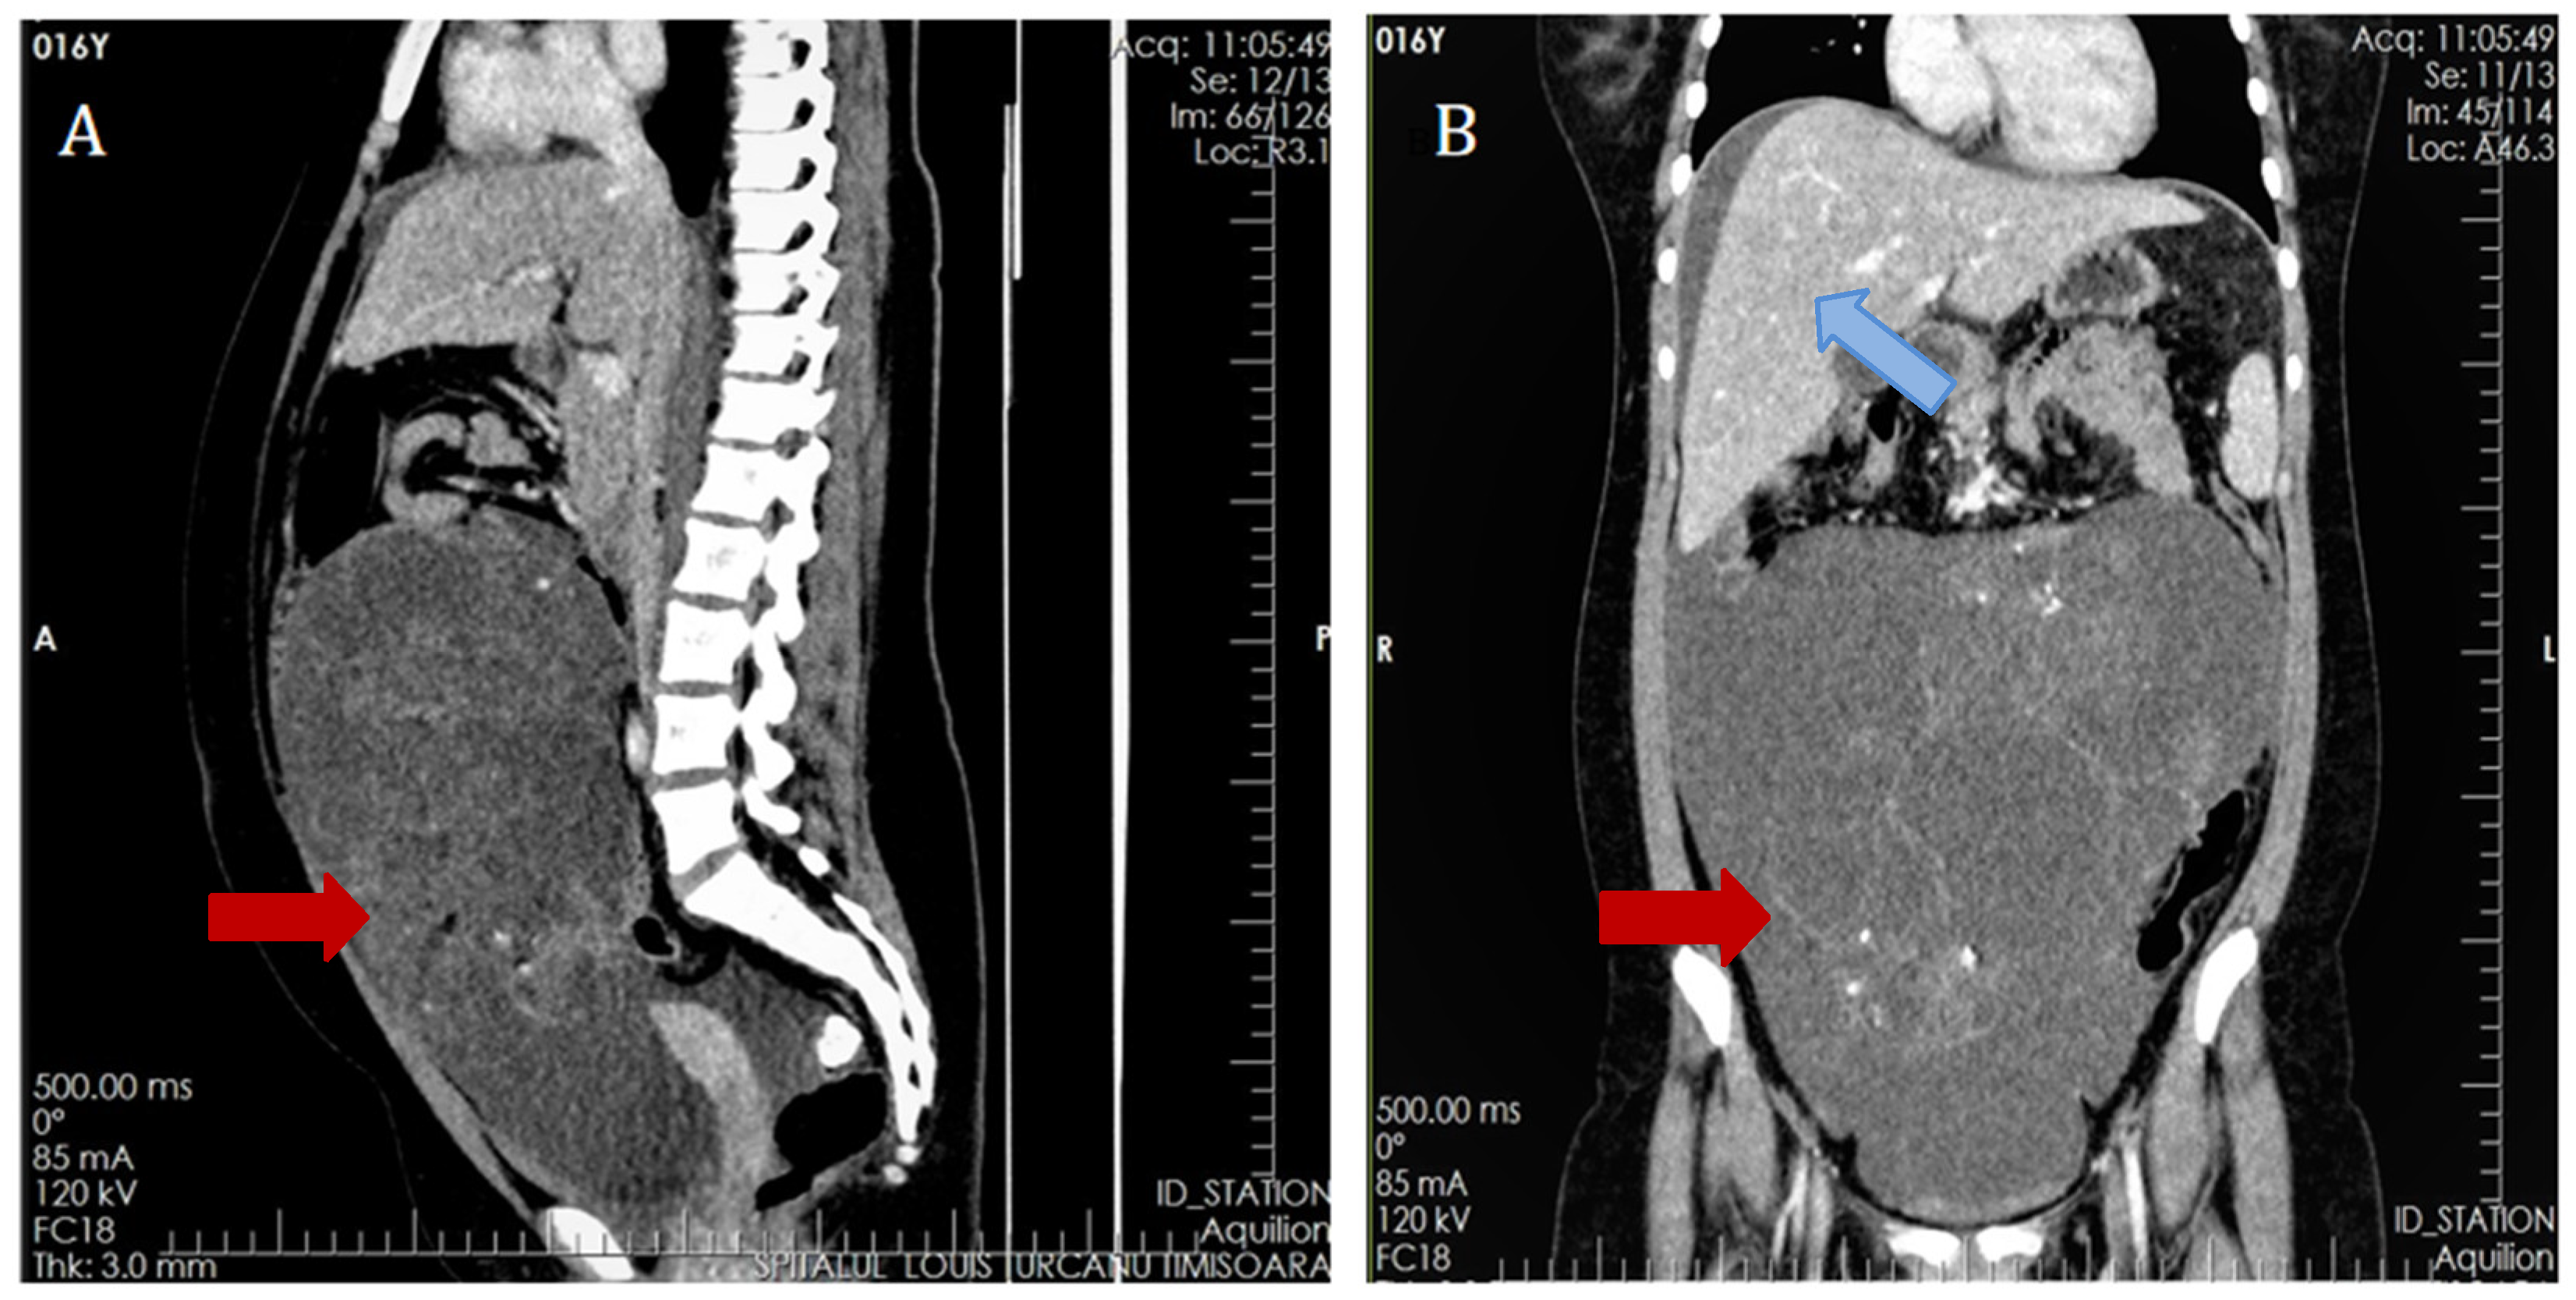

2. Case Presentation